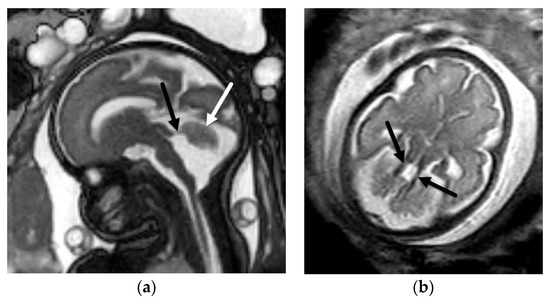

5.2. Other Abnormalities of the Cerebellar Hemispheres

- Poretti, A.; Huisman, T.A.G.M.; Scheer, I.; Boltshauser, E. Joubert syndrome and related disorders: Spectrum of neuroimaging findings in 75 patients. Am. J. Neuroradiol. 2011, 32, 1459–1463. [Google Scholar] [CrossRef] [Green Version]

- Parisi, M.A. The molecular genetics of Joubert syndrome and related ciliopathies: The challenges of genetic and phenotypic heterogeneity. Transl. Sci. Rare Dis. 2019, 4, 25–49. [Google Scholar] [CrossRef] [Green Version]

- Guimaraes, C.V.A.; Dahmoush, H.M. Imaging phenotype correlation with molecular and molecular pathway defects in malformations of cortical development. Pediatr. Radiol. 2020, 50, 1974–1987. [Google Scholar] [CrossRef]